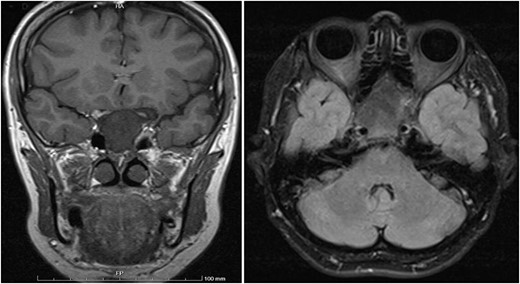

A 56-year-old female presented with a 1-year history of intermittent headaches, which had been increasing in severity and intensity over the last 2 months. The headache was mainly in the right parietal region, throbbing in nature and did not display diurnal variation. The severity of the headache was stated as 7–8 degrees on the Numerical Rating Pain Scale (NRPS; [6]). The pain was partially relieved with analgesia (acetominophen and ibuprofen). She also complained of mild right nasal congestion and intermittent mild otalgia. Physical examination was normal apart from nasal septal deviation. Computed tomography (CT) of the paranasal sinuses showed expansion of the sphenoid bone demonstrating diffuse ground-glass matrix and sclerosis obliterating the sphenoid sinus cavity (Fig. 1). Magnetic resonance imaging (MRI) was highly suggestive of fibrous dysplasia of the sphenoid bone, which appeared as expanded mass with dark T2 signal and T1 hypointense signal (Figs 2 and 3). Near-total excisional biopsy was performed using endoscopic transeptal approach to sphenoid sinuses. Histopathological examination of several pieces of greyish tan and brown bony tissue measuring 3.5 × 2.5 × 1.7 cm. showed branching irregular trabeculae of woven bone with intervening hypocellular fibrous stroma, consistent with a diagnosis of FD (Fig. 4). The patient’s headaches improved greatly following surgery. Two years post-op she reports infrequent headache with a severity of 2 on NRPS.

T1 axial and coronal post-contrast images show some heterogeneous enhancement compared to pre contrast images.